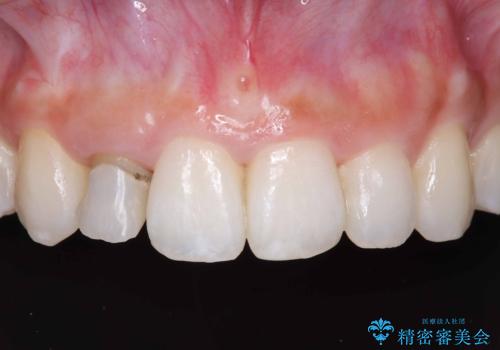

- 「前歯の見た目が気になる」を主訴に来院された患者様です。

オールセラミッククラウンで治療を行いました。

被せ物と歯の境の位置が歯肉の上に設定されており、それによって審美障害が起きていました。